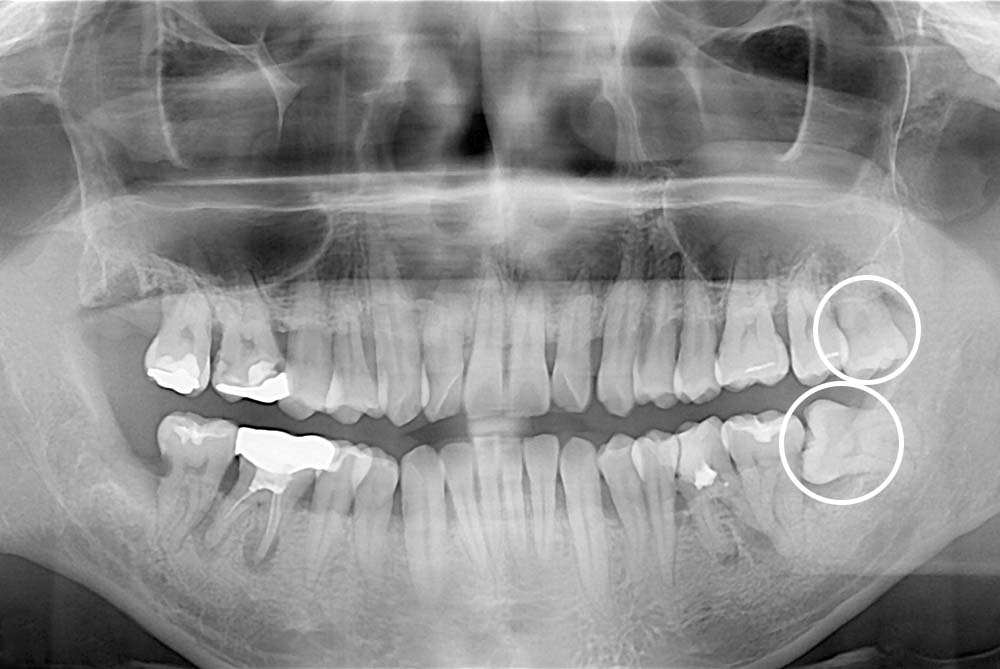

[사랑니] 매복 사랑니 발치

치료전 : 2019-06-28